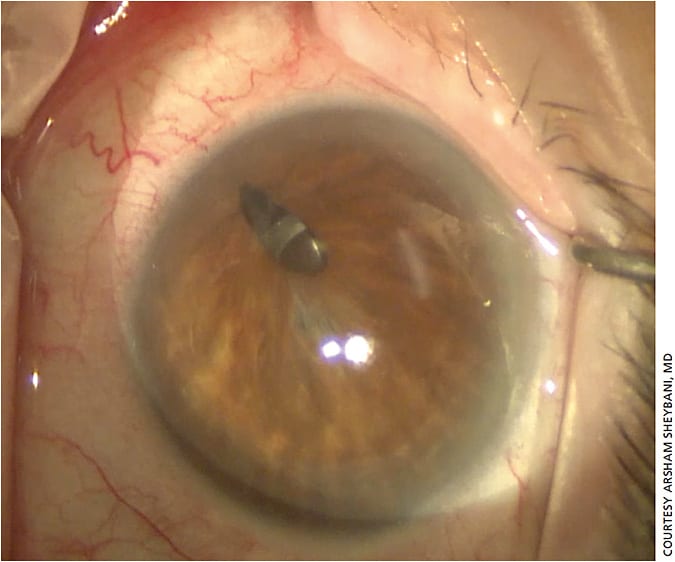

Asymptomatic patients are trickier, Dr. Sheybani notes. For example, in cases of corectopia, patients may end up with double vision because some light will go through the IOL while some may go around it only after cataract surgery is performed (Figure 4). But, suturing can sometimes cause more harm than good, he warns, especially if the iris is highly atrophic (Figure 5).

“In those instances, I consider using a prosthetic iris segment,” he says, adding that several devices are not approved in the United States, so surgeons may need permission from an institutional review board before using them in surgery.